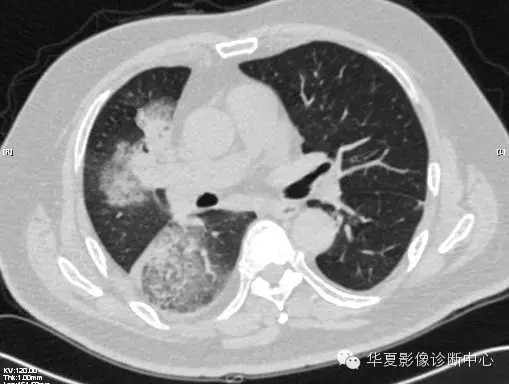

【病例学习】甲型H7N9禽流感一例

男性 63

发热咳嗽5天

2013-4-5拍片示右肺实变,收入院,追问病史,发病期间肌肉酸痛,头痛,无腹痛腹泻,无明显胸闷气急,无意识改变。有高血压病史,无其它病史。

2013-4-7CT进一步检查。

最终诊断:H7N9。